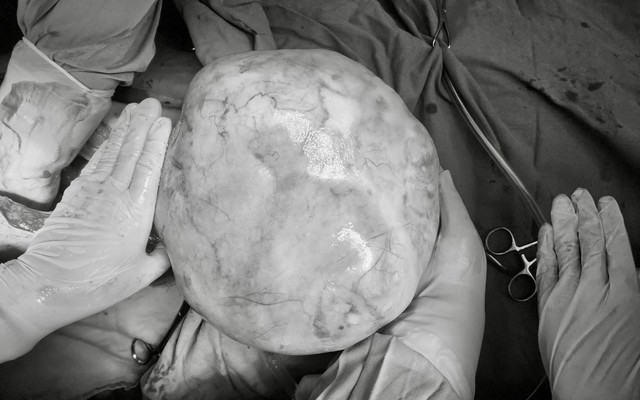

Bé gái 14 tuổi được phẫu thuật loại bỏ u buồng trứng "khổng lồ" Khối u buồng trứng của bé gái nặng tới 4,3kg (Ảnh: BV)

Khối u buồng trứng của bé gái nặng tới 4,3kg (Ảnh: BV)

May mắn là nhờ sự nỗ lực của đội ngu y bác sĩ, ca phẫu thuật đã thành công rực rỡ khi khối u 4,3kg chứa đầy tóc, răng và xương được bóc tách hoàn toàn. Đồng thời, phần tổ chức lành bên buồng trứng trái cũng được giữ lại, đảm bảo tương lai làm mẹ cho bé gái sau này.